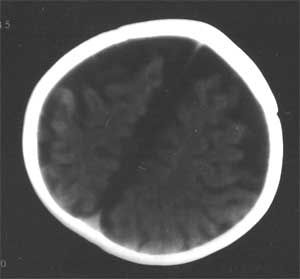

幕上幕下脑室、脑池、脑沟均见扩张积液,考虑脑发育不良。片子质量不好,前囟门似乎偏小,颅骨骨缝不知是否有闭合。9个月幼儿,头围应该不小于40厘米,请测量头围周径。应该没有胼胝体发育不良。至于“右侧基底节区缺血性改变”,片子质量差,看不清楚。

粗看:1。双侧额颞顶叶均有不同程度萎缩,脑实质变薄,2。脑室系统对称性扩张,大脑沟裂增宽变深。3。双基底节区未见明确低密灶,胼胝体发育良好。综上所述考虑有:1)大脑发育不良;2)严重脑缺血缺氧性脑病后遗症?个人意见仅供参考。

脑容量不够,脑沟裂增深增宽,脑室系统扩大。片子质量有问题,暂考虑:以脑发育不全为首诊。

quht先生(女士):首先对你姑娘的这种情况表示关切,不知姑娘临床情况如何。本人曾经是一位儿科大夫,从小儿9个月大小看,运动发育是明显滞后的,三翻六坐七滚八爬,另外感知及情感发育情况如何,可能的话请提供一下,结合ct图片,胼胝体的膝部不连续,蛛网膜下腔、脑沟裂明显增宽,联系起来看,病儿大脑在发育上是存在问题的,蛛网膜下腔增宽有一部分小儿随着年龄的增长会有所好转或改善,胼胝体年龄增长改善的可能性不大。不过如果情感及认知能力还可以,单纯运动发育的滞后还应注意几个问题:病儿现在有几颗牙齿,是否有佝偻病(缺钙)的相关表现,佝偻病运动发育也可滞后。

前纵裂池与三脑室相连,无明显侧脑室分离,可能胼胝体前部发育不全。两额顶部脑组织量减少,脑沟裂增宽,脑室扩大,肯定大脑发育不全,智力会受影响,现在该能看出来吧,孩子反应怎样。